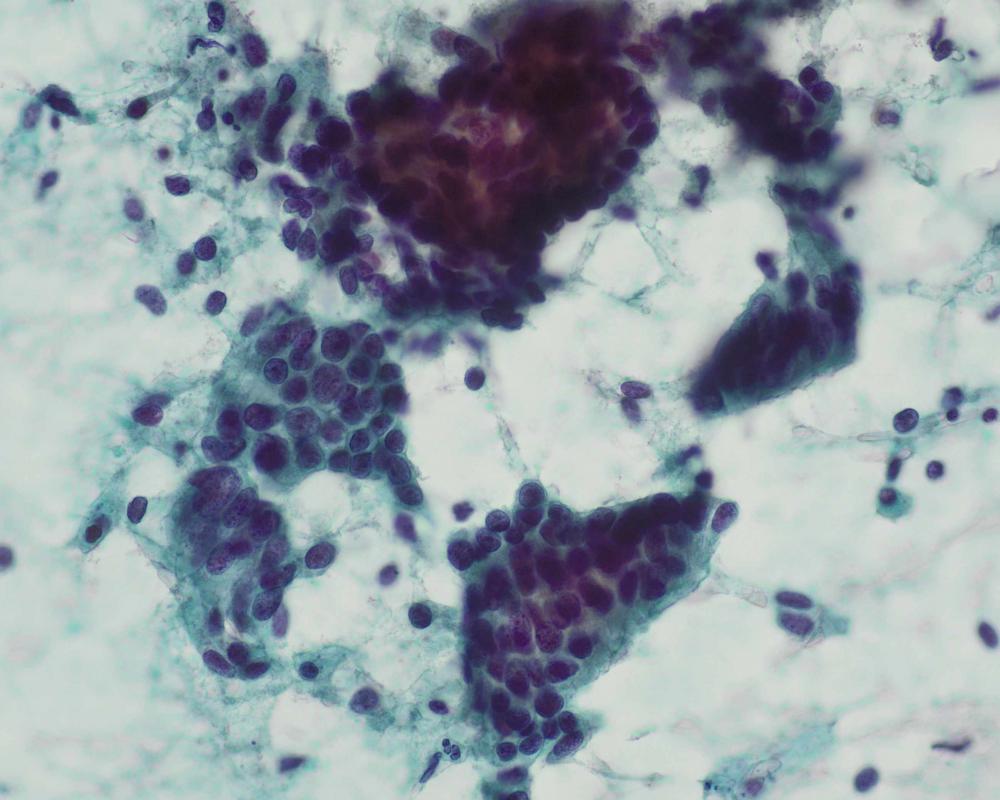

種別:呼吸器

| 採取部位 | 肺腫瘍 | 採取方法 | 捺印 |

既往歴:59歳 前立腺癌に対してホルモン治療、放射線治療、59歳高血圧、63歳糖尿病で内服加療中

現病歴:前立腺癌の経過観察のCTにて右肺結節を指摘された。PSA含めて腫瘍マーカーは正常であった。本標本は術中迅速組織診断用に提出された肺腫瘍の捺印細胞診検体である。

| 正解 | 5.転移性肺腫瘍(前立腺癌) |